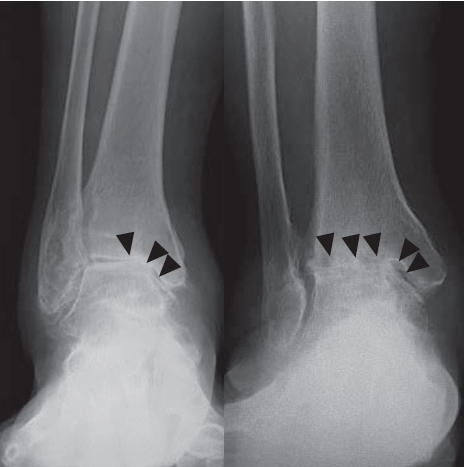

変形性足関節症の診断

足首の痛みの場所や可動域の確認します。次にレントゲン、特に体重をかけた時のレントゲン画像で足首の関節の隙間があるかどうかを確認します。